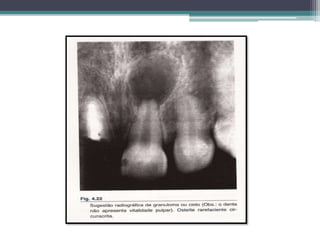

• RADIOGRAFICAMENTE: osteíte rarefaciente circunscrita,

mas existe algumas condições para a sugestão radiográfica da

lesão;

• Caracteristicas Radiograficas:

Não existe diferenças radiograficas entre C.P.A

e G.P

Osteite Rarefaciente circunscrita